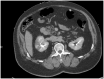

Atrial fibrillation (AF) can cause thrombi formation and subsequent emboli deposition in systemic arteries, leading to various organ ischemia and infarction. Anticoagulation therapy can reduce the risk of thrombus formation and embolization, and is initiated based on a patient's risk score, which is frequently estimated with the CHA2DS2-VASc score. We present a case of thromboembolism (TE) where a low CHA2DS2-VASc score suggested a low-moderate risk of systemic embolization, but an elevated plasma D-dimer value prompted further investigation which revealed an intracardiac thrombus with renal embolism. The patient is a 63-year-old male with past medical history of hypertension and AF treated with ablation 2 years prior presenting with sharp right flank pain of 5-hour duration. Primary workup and imaging were unrevealing at the time, and a low CHA2DS2-VASc score was suggestive of aspirin therapy. However, an elevated D-dimer of 289 ng/mL and a transient increase in creatinine pointed to possible etiology of embolic origin. The diagnosis was confirmed with computed tomography (CT) with contrast and transesophageal echocardiogram, revealing renal infarcts and the source of the emboli, respectively. The patient was treated with heparin and transitioned to apixaban prior to discharge with full resolution of symptoms. Through this case, we wish to show D-dimer's predictive value of TE, as well as its potential benefit in risk assessment in patients with AF.